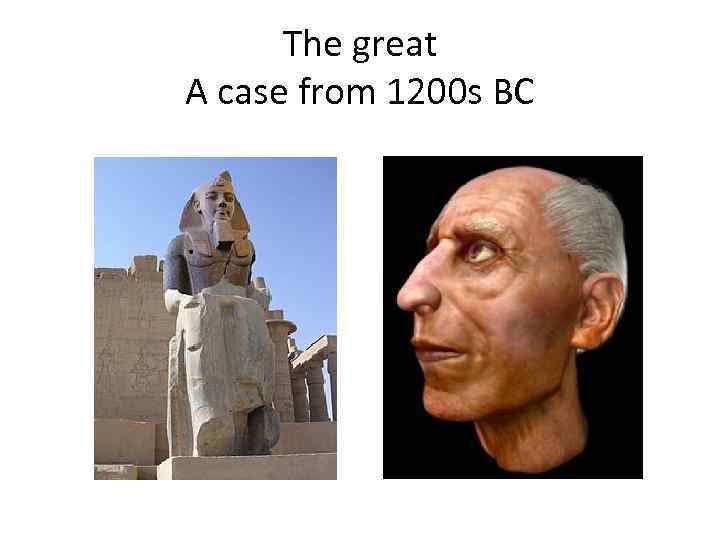

The great A case from 1200 s BC

The great A case from 1200 s BC